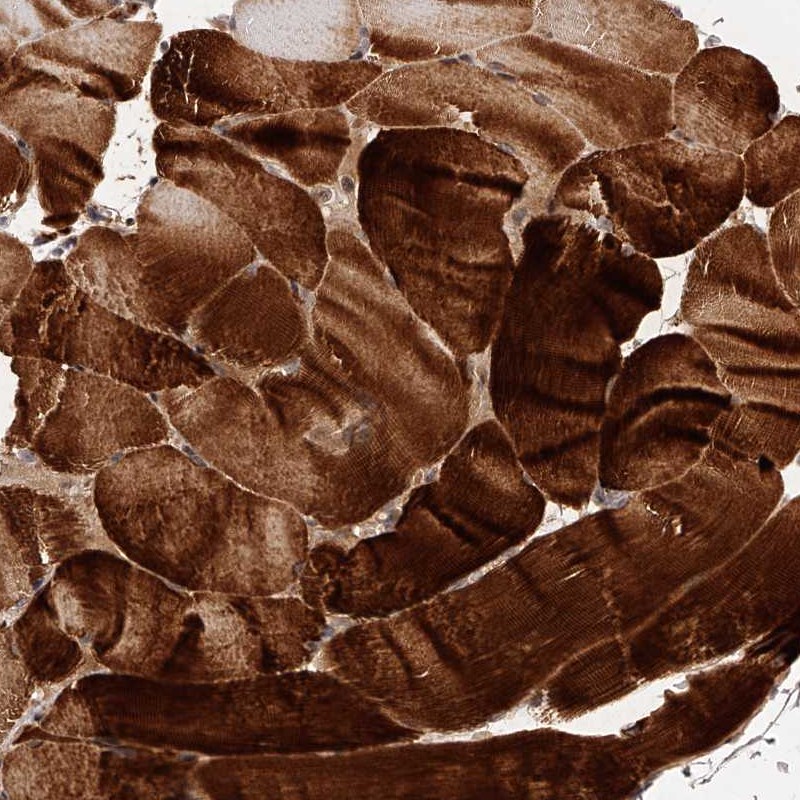

Immunohistochemical staining of human skeletal muscle shows strong cytoplasmic positivity.